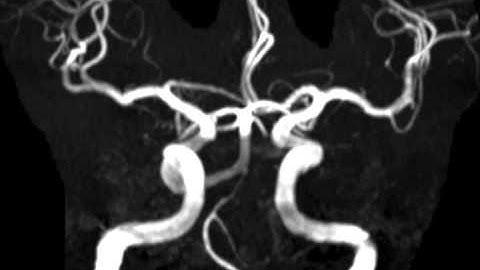

Persistent Trigeminal Artery